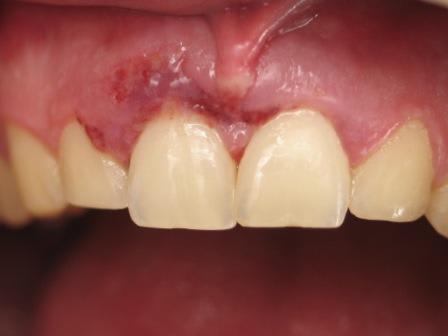

bilan 2 incisives centrales cassées net 1,5 mm sous le rebord alvéolaire

quelques photos au courant de la journée

Image odged8 - Eugenol

enfin et surtout : si tu regardes la photo initiale tu peux constater l'état inflammatoire important de la gencive : donc la temporisation telle que je l'ai faite (dévit + tenon radiculaire) est celle qui selon MON intuition du moment, permettra une cicatrisation rapide indispensable pour procéder à l'extraction implantation immédiate et mise en cosmétique .